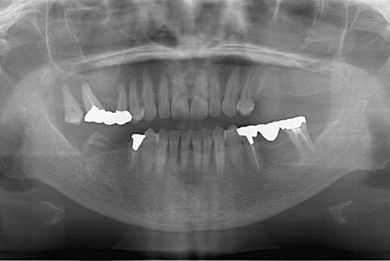

| 性別/年齢 | 女性 / 59歳 | ||||||||||||||||||||||||||||||||

| 主訴 | 奥歯がないので、インプラントか入れ歯の相談をしたい。 | ||||||||||||||||||||||||||||||||

| 治療方針 | 左上奥ソケットリフトにて上顎洞を拳上、骨再生法を行い、インプラント治療を可能にする。 | ||||||||||||||||||||||||||||||||

| 治療内容 | インプラント4本(GBR)、ハイブリッドセラミック4本 | ||||||||||||||||||||||||||||||||

| 総治療費 | 1,680,000円 | ||||||||||||||||||||||||||||||||

| 治療期間 | 11ヶ月 |